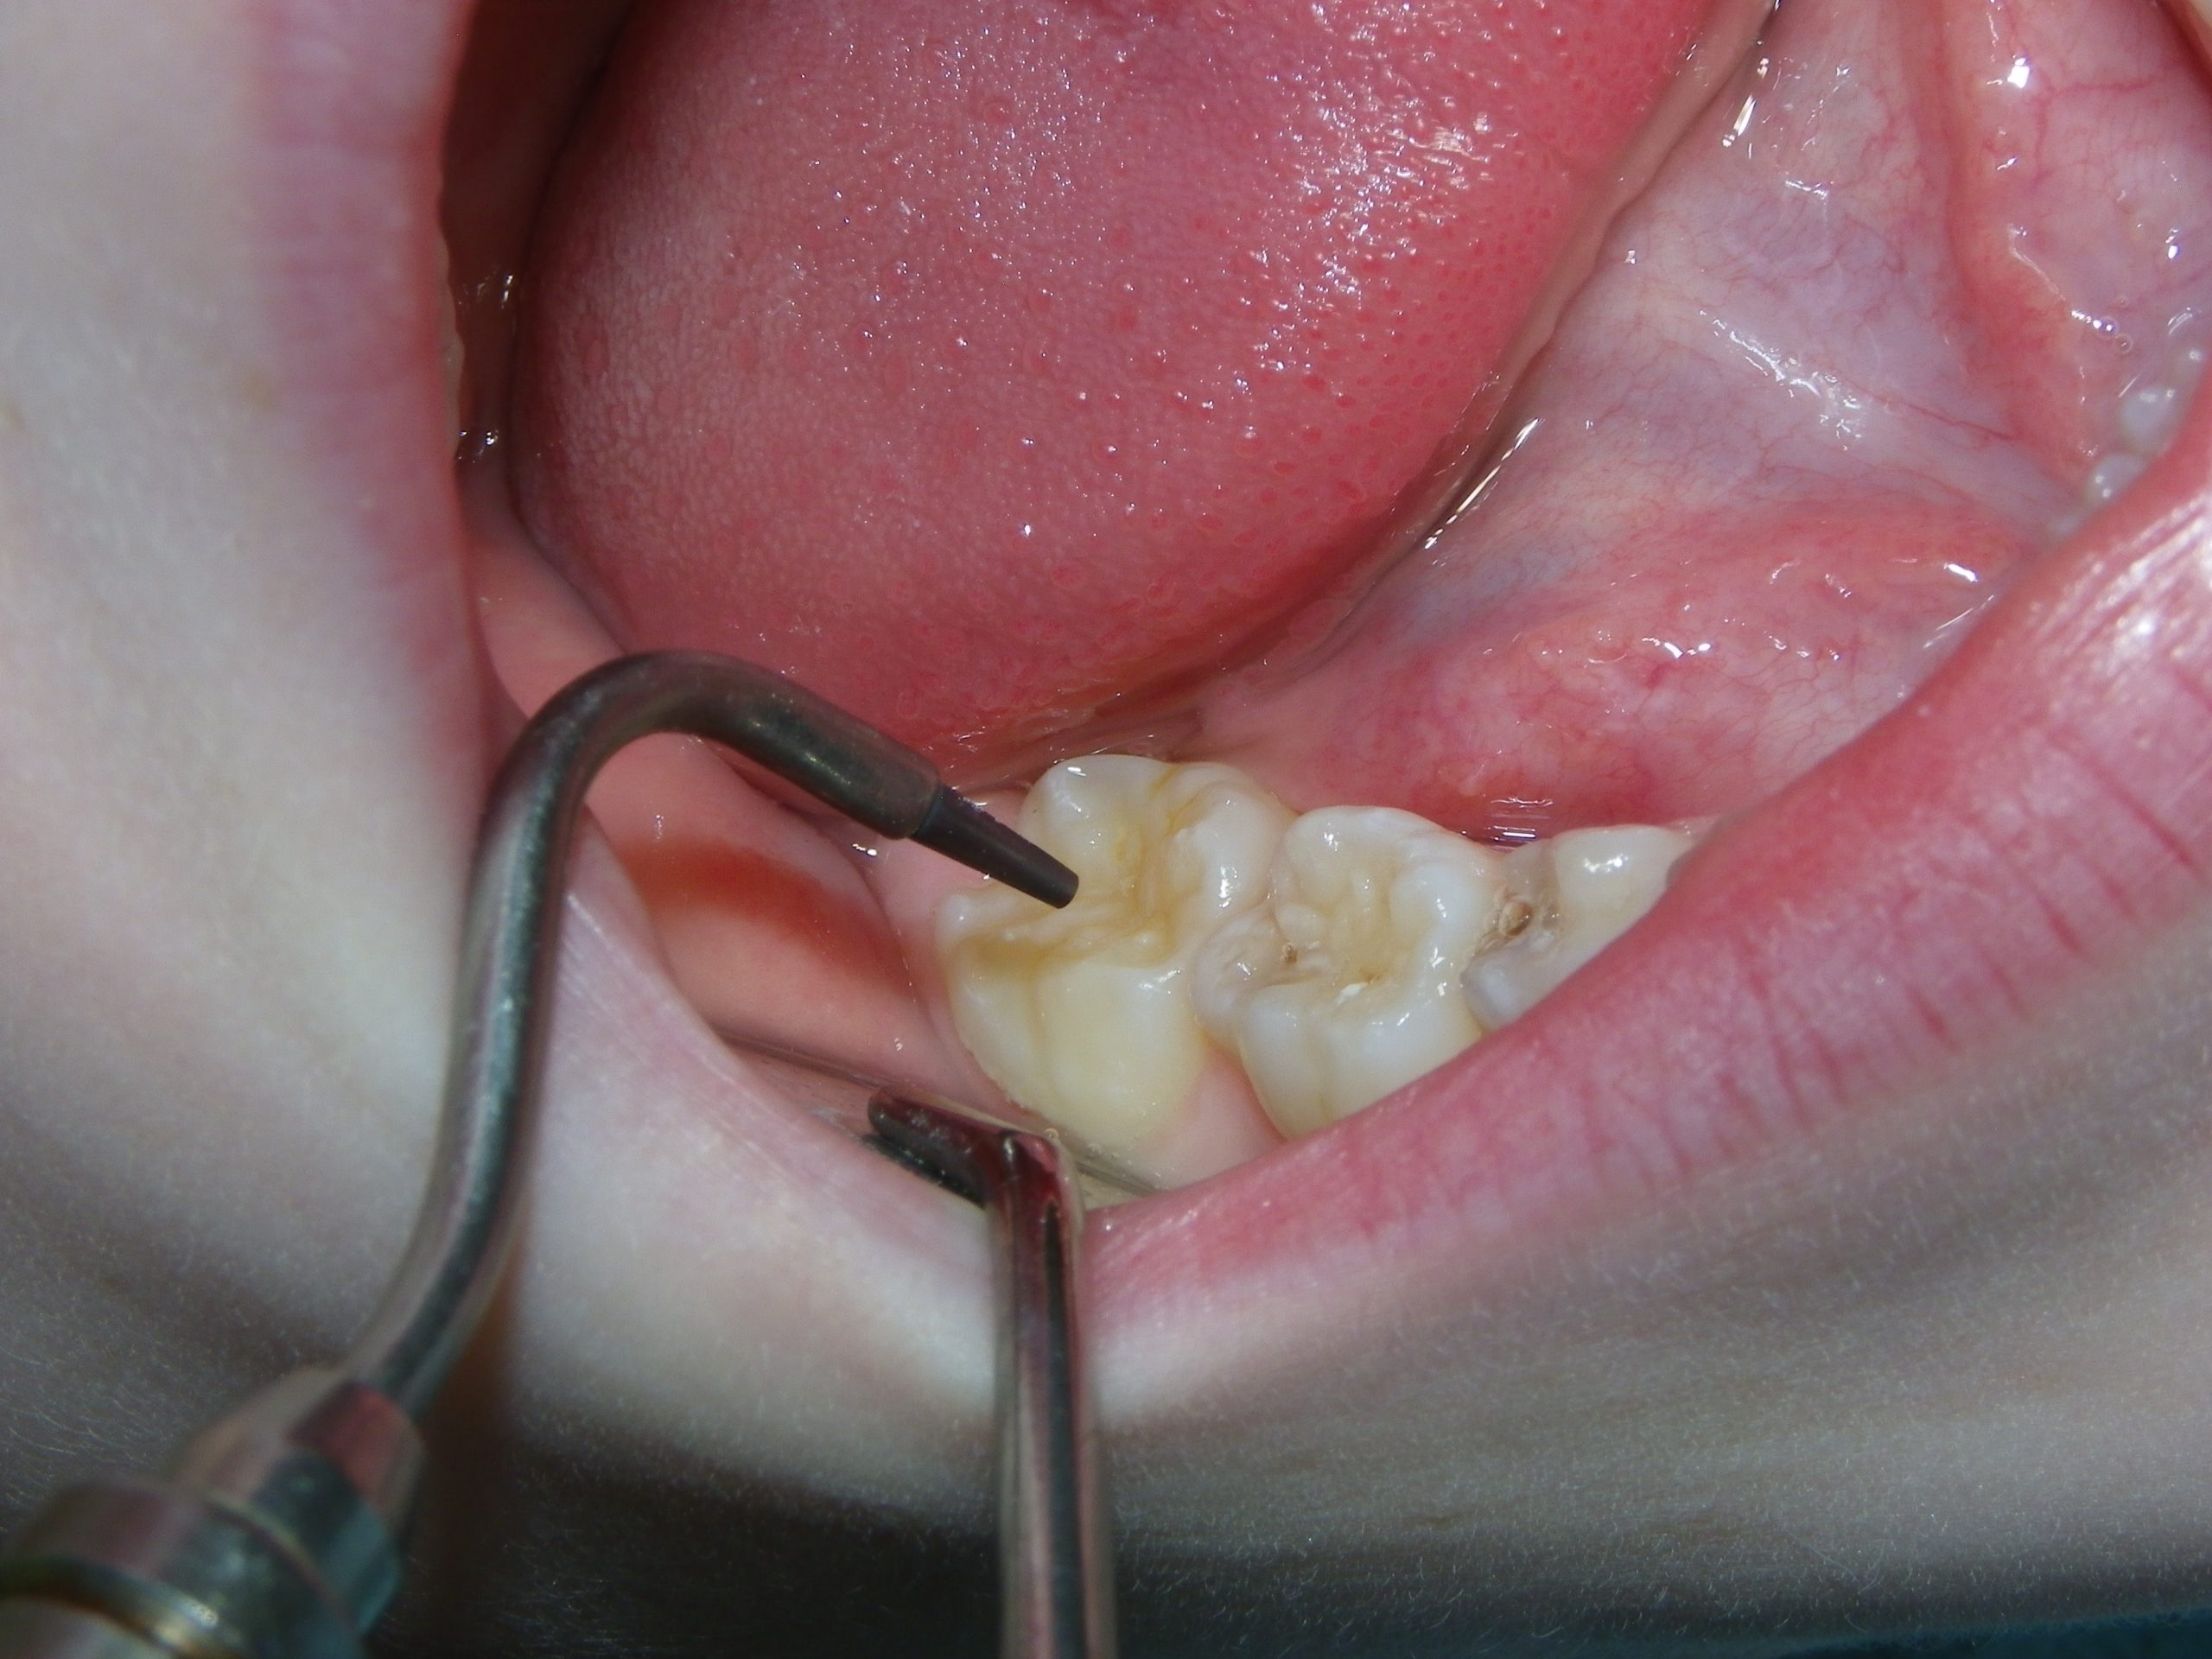

This quick photo series shows the step-by-step process of placing a sealant onto the grooves of an adult molar of a six-year-old. First, air abrasion is used to mechanically remove any loose surface debris or contaminants. Secondly, an acid gel is applied to the surface to be sealed. Finally, a sealant is applied to the surface and allowed to set. For the sharp-eyed, the sealant used was GC Fuji Triage, a glass ionomer sealant that while not as wear-resistant as the more commonly used resin sealants, is more moisture-friendly (ie: contamination resistant) and releases fluoride. The fluoride release allows the underlying enamel to be strengthened over time, making it more decay-resistant for the future.